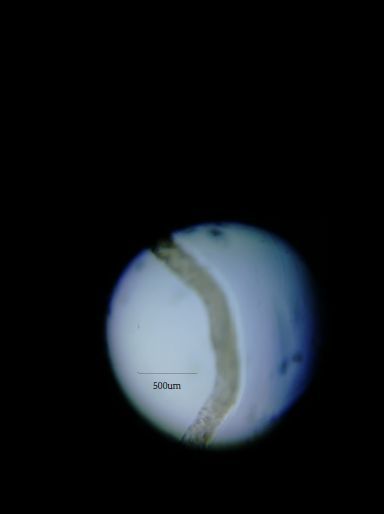

Schistosoma

140x Magnification